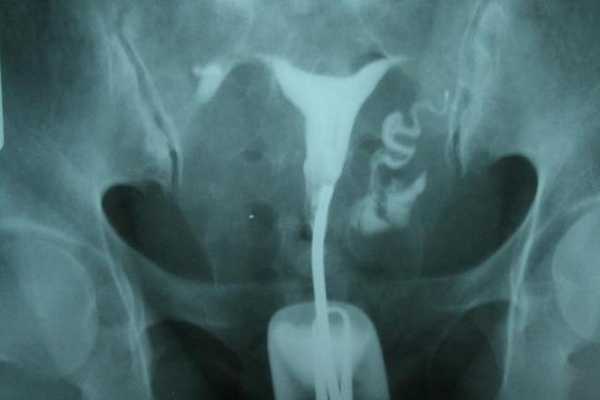

- гистеросальпингография (рентгенологическое исследование матки и труб);

- диагностическая лапароскопия (позволяет получить наиболее точную информацию, видны утолщенные трубы с просвечивающимся водянистым содержимым).